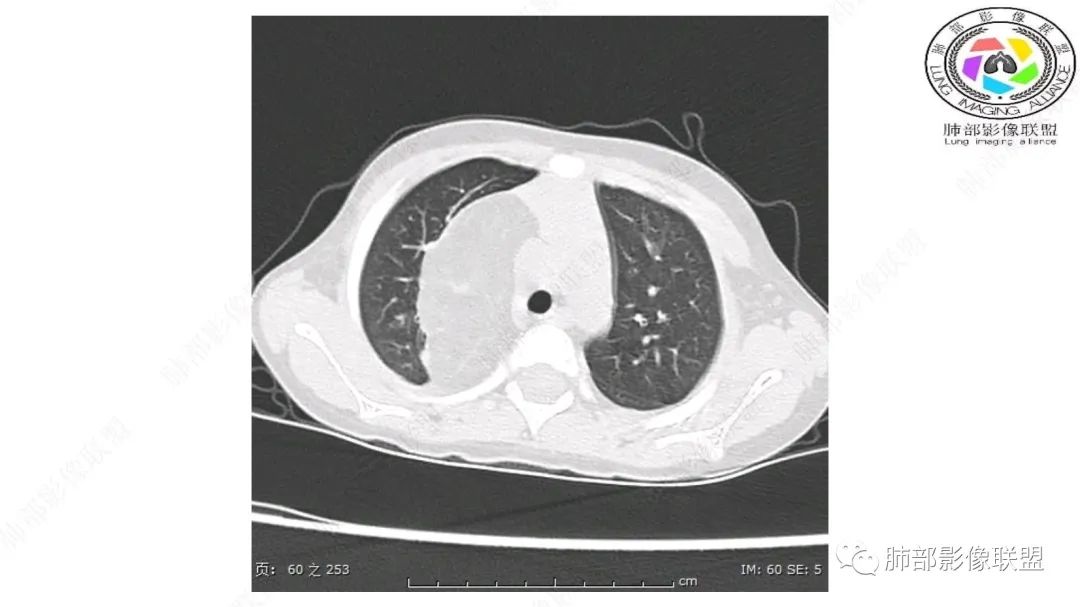

三岁小儿,右侧纵隔巨大脂肪密度肿块,肺动脉穿行其中,密度欠均匀,未见明确实性成分,纵隔脂肪母细胞瘤,冬眠瘤鉴别纵隔脂肪增多症(多弥漫对称)。

患儿3岁 咳嗽检查发现纵隔占位。右肺上叶受压表现,占位以脂肪组织密度为主,似见分隔,首先考虑为脂肪母细胞瘤,鉴别脂肪瘤,畸胎瘤。

幼儿,右上纵隔团块状脂肪密度影,边缘清晰,内可见血管及支气管穿行,考虑脂肪瘤,鉴别畸胎瘤。

幼儿,右上纵膈团块,脂肪密度,内见分隔,增强病灶内见血管穿行,结合患者年龄,考虑脂肪母细胞瘤,鉴别脂肪瘤。

病灶属于交界区,主体位于肺内,占位效应明显,前方突入胸壁,胸腺受压变形,胸膜显示欠清楚;病灶包绕上叶肺动脉;似乎有体动脉供血。符合肺内的点:包绕上叶肺动脉分支;符合纵隔的点:前方似乎突入胸壁,与胸腺关系比较密切,但是与上腔静脉的关系提示病灶不支持纵隔来源,前纵隔的常规会将上腔静脉受压后移、外移,这是不符合的。

2.肺动脉穿行也许是肺内来源最重要支持点!

CT扫描对脂肪类肿瘤常有独到价值。肿块孤立、边界清楚,未见周围浸润,较均匀脂肪样低密度,高度提示为良性!